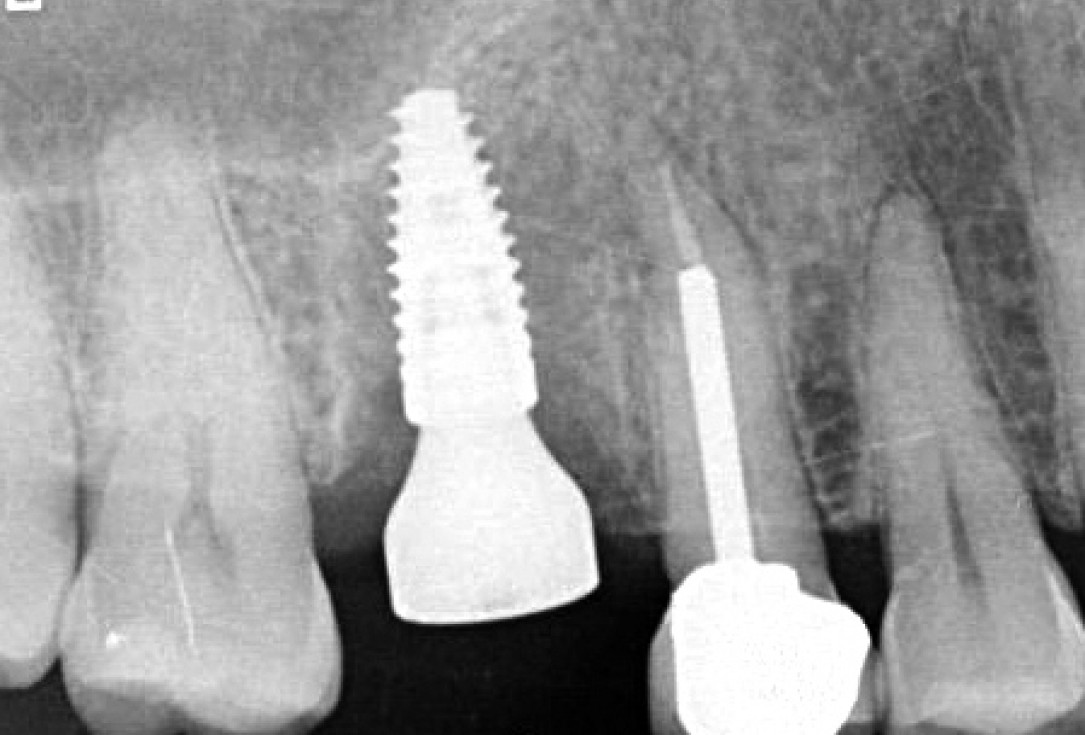

5/11 - Planing of implant positioningSealing of a postextraction socket with mucoderm® - Dr. M. Frosecchi

6/11 - Implant placementSealing of a postextraction socket with mucoderm® - Dr. M. Frosecchi